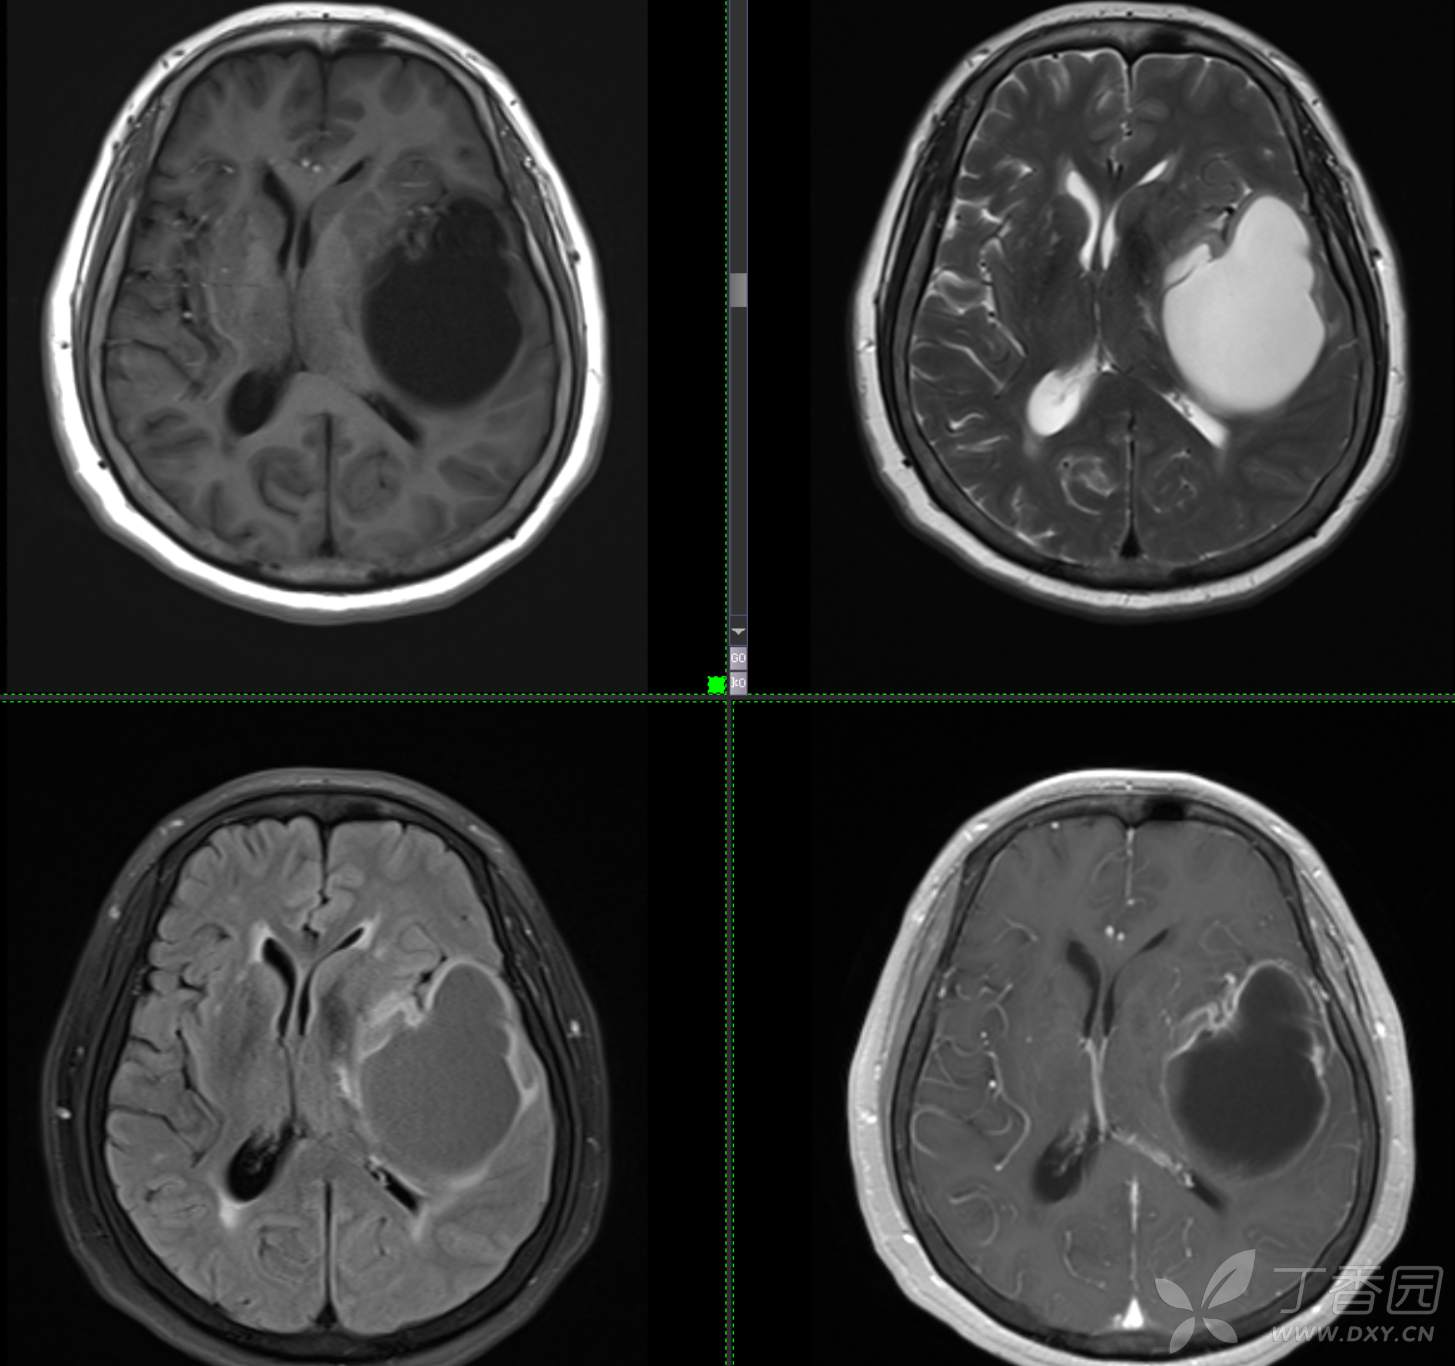

现病史: 【患者1月余前无明显诱因出现记忆力减退,易忘记事情,表现为忘记说过的话、易忘 事、理解力及计算力均尚可、阅读无受限、无性格脾气改变,无头痛头晕、无恶心呕吐、无视物模糊,无言语不利,无幻觉妄想,当时未重视未就诊。1月内记忆力减退进行性加重,对刚做过的事情即遗忘,计算力下降,日常生活尚能自理。遂至我院门诊就诊,查“颅脑CT平扫:左侧基底节-颞叶区低密度占位,建议进一步增强 MRI检查。

患者既往子宫内膜癌手术史;高血压病史3年